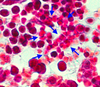

megakaryocyte (bone marrow)

highlighted area

red cell nest (bone marrow)

highlighted area